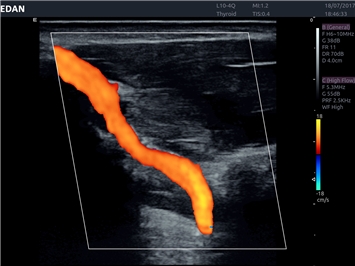

• Автоматическое измерение толщины интима-медиа

• Сосудистой диагностики

Цветовой допплер:

Да

IMT (Intima Media thickness):